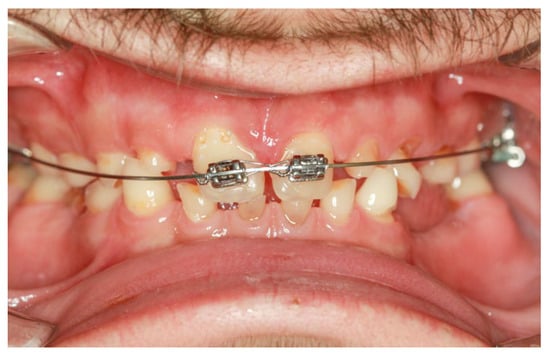

Preprosthetic orthodontic treatment was conducted with a partial fixed appliance (transpalatal bar and 0.022-inch Roth prescription brackets on the 11 and 21). The main objective of this treatment phase was to reduce the diastema and slightly retrude the upper incisor to improve the dental position for the final restorations (Figure 6).

Figure 6.

Intraoral clinical aspect during the orthodontic treatment.